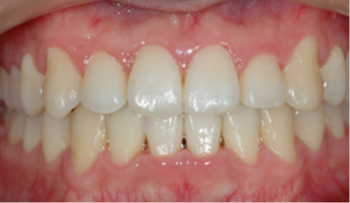

그 결과, 기능을 회복하고 아름다운 얼굴 모양을 완성할 수 있습니다.

결국, 교정 치료란 치아 기능을 회복해 균형 잡힌 아름다움을 만드는 일입니다.

치료(유지)

교정 치료를 통해 개선된 치열 상태가 오랫동안 유지되도록